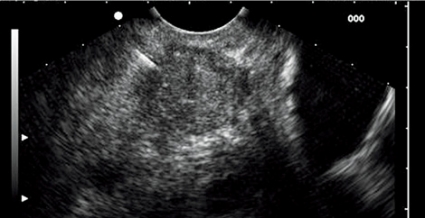

Betydelsen av endoskopiskt ultraljud vid akut pankreatit är inte säkerställd, men metoden kan vara av värde för diagnostik vid gallstensinducerad pankreatit och för selektion av patienter inför ERCP. En ny studie rapporterade att endoskopiskt ultraljud är mer kostnadseffektivt än ERCP och MRCP (magnetisk resonanskolangiopankreatografi) vid akut biliär pankreatit [15]. Vid kronisk pankreatit kan endoskopiskt ultraljud underlätta diagnosen genom bedömning av fokala förändringar i parenkymet och förändringar i pankreasgången [16] (Figur 10). I dag råder också bred konsensus om att patienter med idiopatisk pankreatit bör genomgå endoskopiskt ultraljud, som i många fall kan klarlägga bakomliggande orsak.